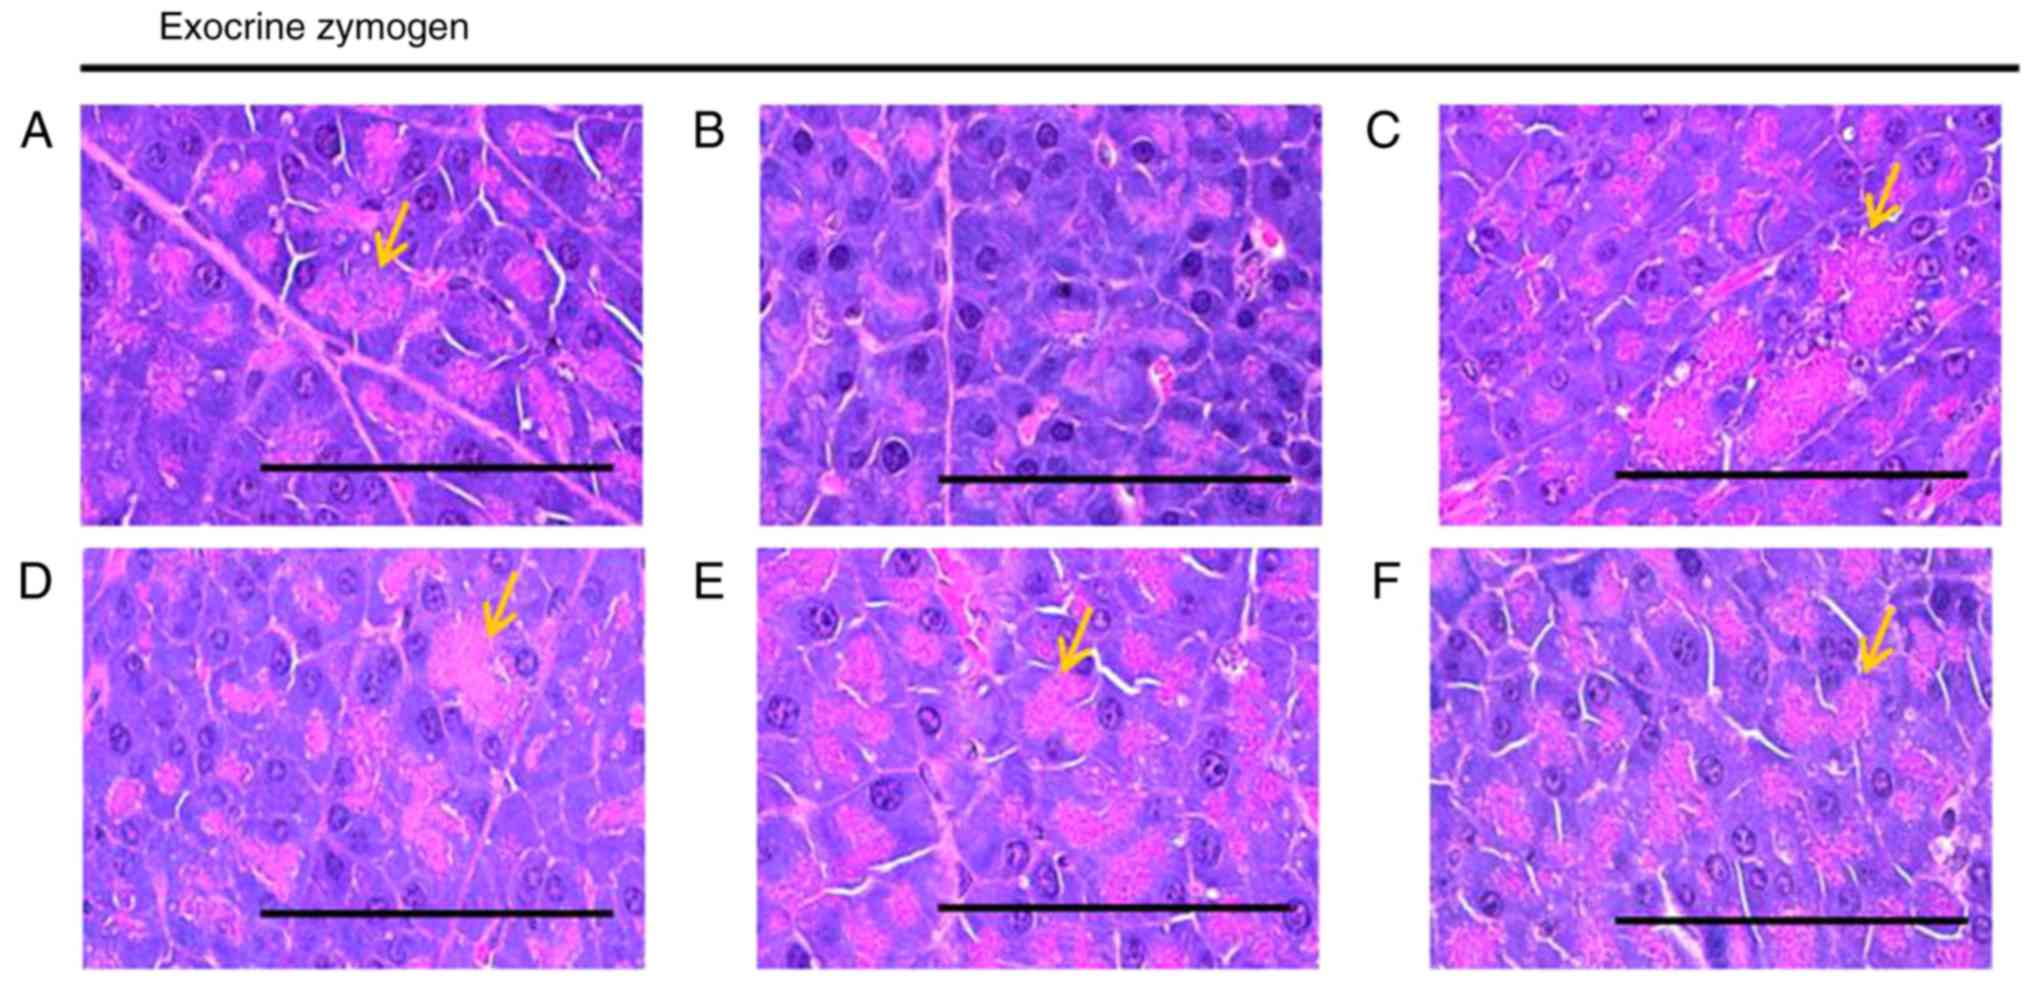

Effects on the exocrine pancreas zymogen

granule content

A significant (P<0.05) decrease in the exocrine

pancreas zymogen granule content (the proportion of exocrine

pancreas occupied by zymogen granules) was observed in the HFD

control group, which resulted from the release of zymogen granules.

The exocrine pancreas zymogen granule content was significantly

(P<0.05) increased in all treatment groups compared with in the

HFD control mice. Specifically, all BHe treatments resulted in

clear dose-dependent increases in the proportion of the regions of

the exocrine pancreas occupied by zymogen granules compared with

that in the HFD control group (Table

V; Fig. 6). The proportion of

the regions of exocrine pancreas occupied by zymogen granules in

the HFD control groups decreased by −68.87% compared with in the

healthy control, with changes of 131.93, 77.07, 103.28 and 156.04%

in the metformin (250 mg/kg) and BHe (400, 200 and 100

mg/kg)-treated groups, respectively.